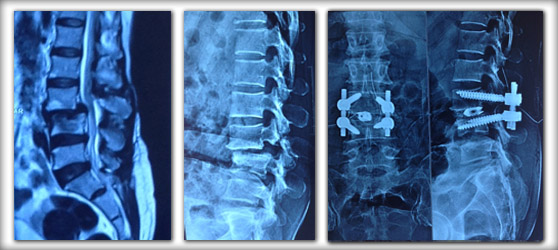

Case Example:

Spondylolisthesis is a condition where is slippage of one vertebra over the other leading to instability and back pain during bending movements of spine. 42yr old house wife who presented with chronic back pain and leg pain not relieving with physiotherapy was found to have L3-L4 spondylolisthesis. Stabilisation and fusion of L3-L4 segment relieved her symptoms.